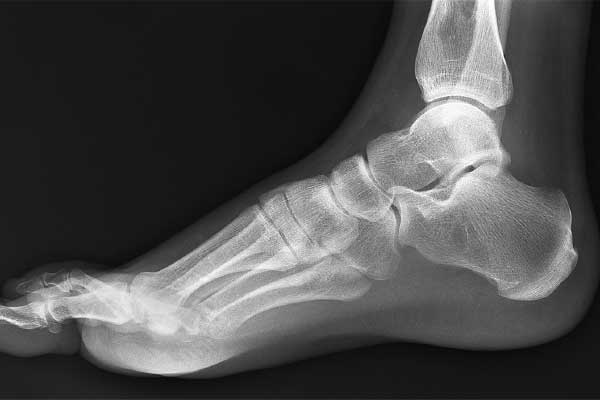

Susan Welch Dear Dr. Carreira, You fused my left subtalar joint in November 2012. The surgery has been a complete success for me. It is life changing in that I am finally pain free after over 30 years of debilitating... Read more about Susan Welch »

Stewart Martin, calcaneus fracture patient treated surgically

Stewart Martin, calcaneus fracture patient treated surgically As a follow-up to my last visit in November, I wanted to let you know I went skiing with my family for a week. After some initial nervousness, I am thrilled to say... Read more about Stewart Martin, calcaneus fracture patient treated surgically »